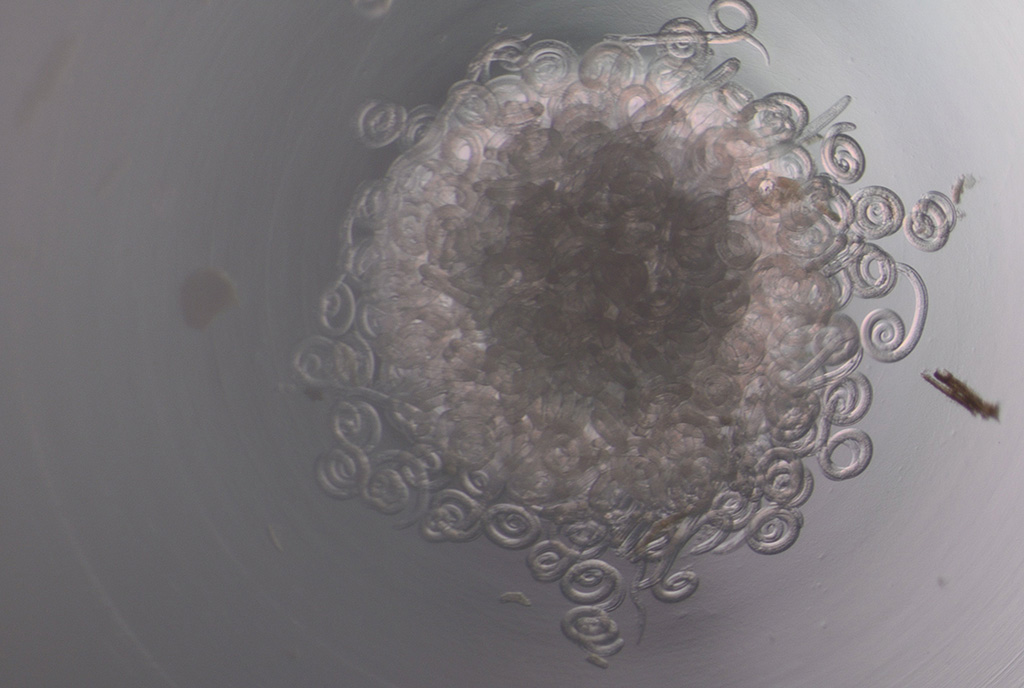

Trichinella mikroskoobi all. Foto: erakogu